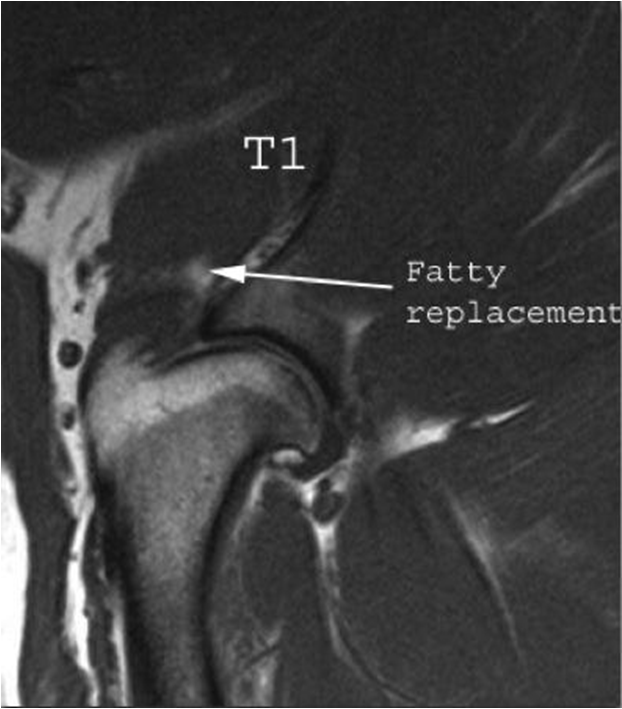

Results: Dogs aged 4 months to 14 years (average 6.5 years; median 6 years) were diagnosed with ST. Performance and sporting dogs were 39.4% of the population, with 58.1% of them being agility dogs. Pain was elicited on palpation of the supraspinatus tendon in 49.3% of dogs. Shoulder radiographs in 283 dogs showed mineralisation in 13% of cases. MRI of the shoulder was performed in 31 cases and revealed findings indicative of ST, including hyperintensity of signal on T1 weighted image (or “spin-lattice”) and Short T1 Inversion Recovery (STIR) sequences of the supraspinatus tendon at its insertion on the greater tubercle and mineralisation of the supraspinatus tendon. Common ultrasonographic findings included increased tendon size (76%), irregular fibre pattern (74%), and non-homogeneous echogenicity (92.5%). The most common findings on shoulder arthroscopy were supraspinatus bulge (82.2%) and subscapularis pathology (62.4%). Elbow pathology was recorded in 54.5% of dogs. Treatment outcomes showed 74.6% of dogs failed to respond to non-steroidal anti-inflammatory drugs (NSAID) and 40.8% failed to respond to rehabilitation.